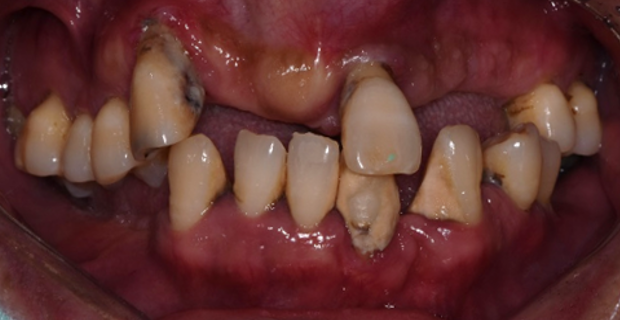

치료 전

40대 남성 환자분으로, 전반적으로 치아들이 치주염에 이환되어 살릴 수 있는 치아가 거의 없었던 경우입니다.

살릴 수 있는 본인의 치아는 꼭 살리고 싶다고 요청하셨습니다.